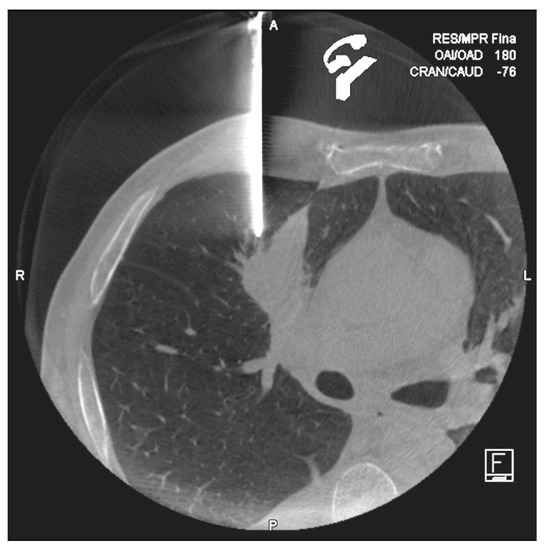

Cone-Beam CT-Guided Lung Biopsies: Results in 94 Patients

2. Materials and Methods